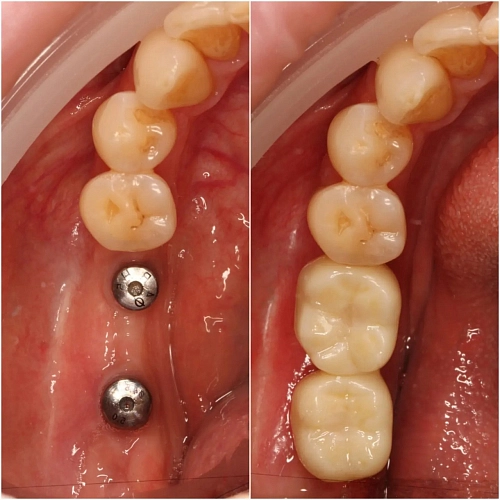

На фото представлен клинический случай.

Протезирование на имплантах с подготовкой костной ткани и десны в позиции зубов 47,47